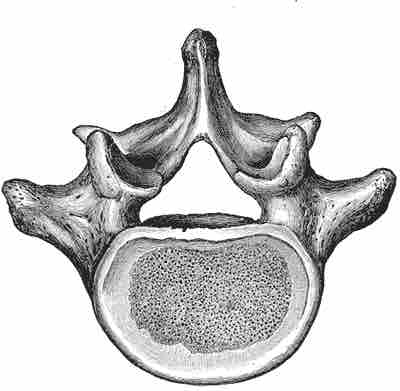

The five lumbar vertebrae are the largest vertebral bones and increase in size when moving inferiorly. The lumbar vertebrae play a key role in supporting the body and facilitating locomotion.

Lumbar vertebra

Image of typical lumbar vertebra.